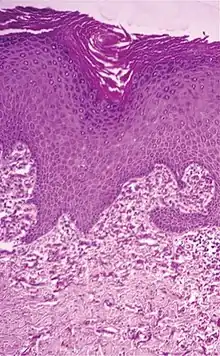

| Actinic elastosis (most common, also called solar elastosis) |

Elastin replacing collagen fibers of the papillary dermis and reticular dermis | ![]() |

| Elastosis perforans serpiginosa | Degenerated elastic fibers and transepidermal perforating canals (arrow in image points at one of them)[11] | ![]() |